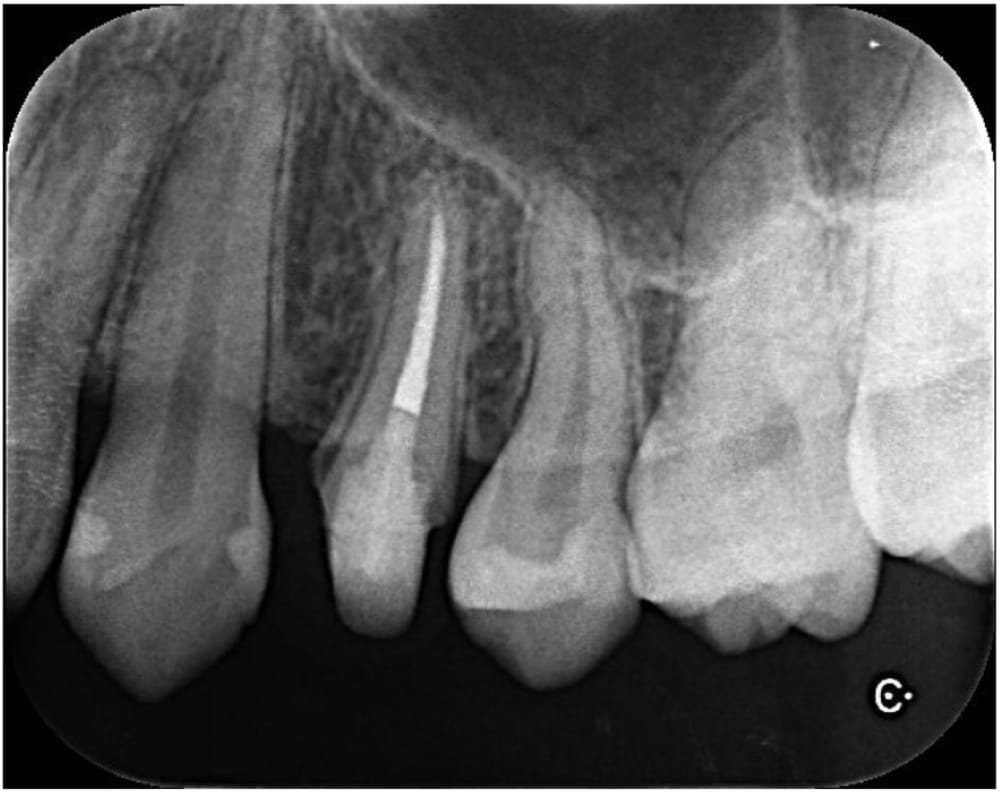

左上の第一小臼歯(4番)には虫歯が認められ、レントゲン・CTにて明瞭な骨吸収像が認められました。痛みなどの症状はないものの、このまま被せ物の治療をやりかえる場合、将来的に根の先の膿が大きくなる可能性があるため、根管治療が第一選択であるとお伝えし、根管治療を開始することになりました。

治療後6ヶ月で根尖部の透過像は縮小傾向を認め経過良好のため、ジルコニアクラウンによる最終補綴治療へ移行しました。